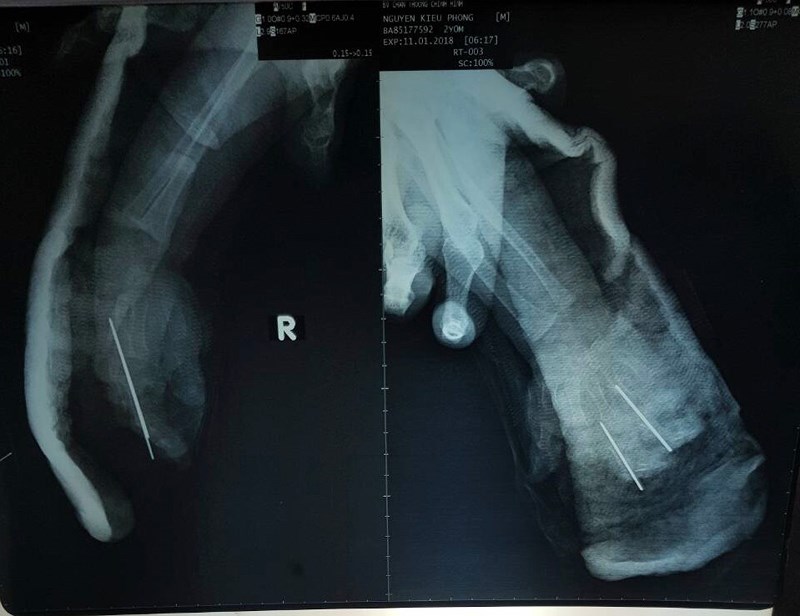

Bé trai ở thị xã Bến Cát, Bình Dương được người nhà đưa tới Bệnh viện Chấn thương chỉnh hình TP.HCM trong tình trạng bàn tay phải bị đứt lìa, ngón bị dập nát.

Ngay lập tức bé được đưa ngay vào phòng phẫu thuật. Ê-kíp bác sĩ đã cắt lọc, nối ghép vi phẫu cứu bàn tay cho bệnh nhi. Ca mổ kéo dài 6 giờ.